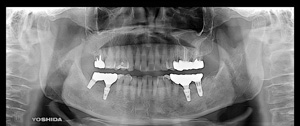

@S.Y‚³‚ñ@ 65Π @’j«@Ž©‰c@@Žèp“ú@‚Q‚O‚O‚W”N@‚UŒŽ‚P‚V“úi‰Îj  ㉺Š{ƒm[ƒxƒ‹ƒKƒCƒhŽg—p@Ö¬“à’ÁÖ@•¹—p

@@@ ㉺Š{  All on ‚U@‘¦Žž‰×d

@    @Rpl Tapered Rp ‚P‚O mm(‚V–{)  @ Rpl Tapered Rp  ‚P‚R mm(‚T–{)@